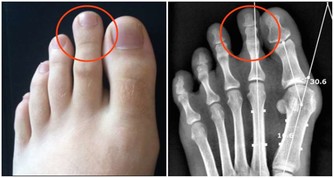

部分高血壓患者,會有頭暈、頭痛、頭脹、耳鳴、眼花等症狀。但也有部分患者,甚至收縮壓都已經180毫米汞柱了,還是自我感覺非常良好,沒有任何不舒服。